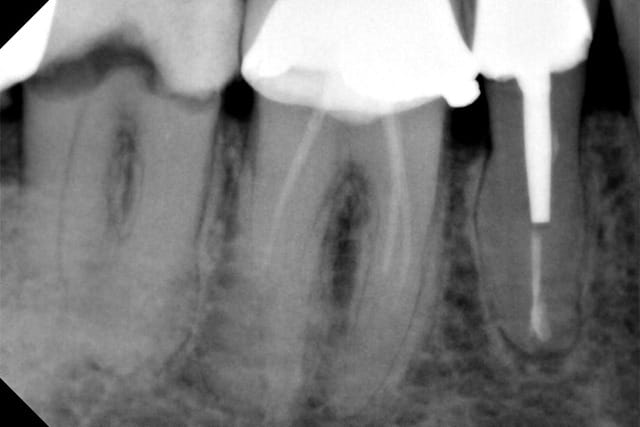

un patient adressé pour endo 47 ou j'ai utilisé les pathfiles puis mise en forme classique

Dardenne 1 oavcsl - Eugenol

Dardenne 2 nz16af - Eugenol

Sur mon cas clinique en mésial la lime 8 manuelle n arrivait qu à mi racine et avec la pathfile équivalente ça m a permis de très vite . progresser. ..

J essaye toujours avec une lime manuelle pour explorer l anatomie de la dent.

mais dans certains ces limes sont vraiment un très gros coup de pouce...